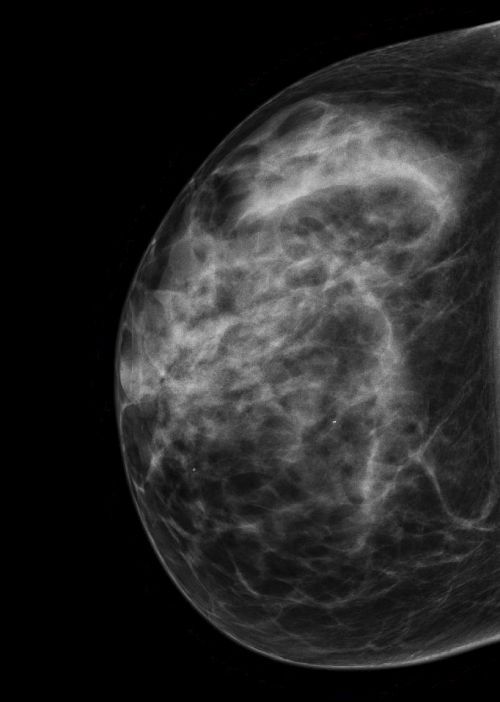

ACR-Klassifikation der Brustdichte in der Mammographie

Die ACR-Klassifikation der Brustdichte in der Mammographie ist ein System zur Einteilung der Brustgewebe in vier Kategorien, die von A bis D reichen. In Deutschland wird der anstatt ACR der Begriff Beurteilbarkeitsstufe verwendet.

Die Kategorie A steht für eine fast vollständig fettreiche Brust, die Kategorie B für eine überwiegend fettreiche Brust mit einigen fibroglandulären Bereichen, die Kategorie C für eine heterogen dichte Brust mit mehreren fibroglandulären Bereichen und die Kategorie D für eine extrem dichte Brust mit sehr wenig Fettgewebe.

Die Brustdichte ist ein wichtiger Faktor für die Erkennung von Brustkrebs, da dichtes Gewebe die Beurteilbarkeit der Mammographie erschweren und mögliche Tumoren verdecken kann. Die ACR-Klassifikation der Brustdichte in der Mammographie hilft den Radiologen, die Aussagekraft der Mammographie zu beurteilen. Je dichter das Drüsengewebe, desto sinnvoller ist eine zusätzliche Methode wie Mamma-Sonographie oder Mamma-MRT.